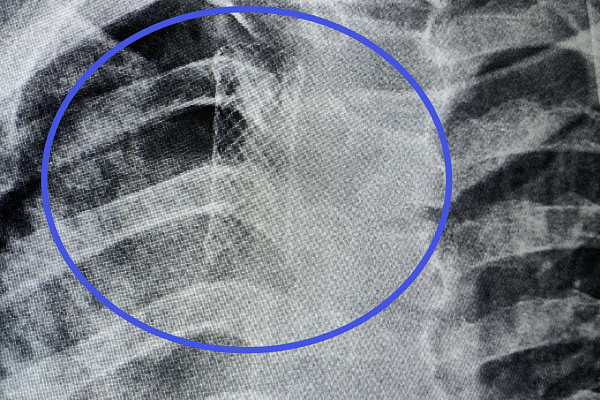

С редким отсроченным послеоперационным осложнением к нам поступил ребёнок. 15-летний пациент был доставлен с пневмотораксом. Из-за скопления воздуха в плевральной полости правое лёгкое настолько сжалось, что перестало участвовать в дыхательном процессе. Причину определили при бронхоскопии: дефект стенки трахеи. 5-миллиметровое отверстие стало местом сообщения с плевральной полостью, нарушив её герметичность, стерильность и вакуум. Воздух из трахеи заполнял пространство, где давление должно оставаться отрицательным, и стеснял лёгкое. Помимо трудностей с дыханием, ситуация может привести к развитию опасных гнойных воспалений плевры и средостения.

В данном случае нарушение целостности трахеи – это осложнение после хирургического вмешательства. Ранее подросток перенес операцию в другом регионе. Ему удаляли новообразование вилочковой железы, и - как возможный источник метастазирования - соседнюю жировую клетчатку и лимфоузлы.

-В жировой клетчатке средостения находятся артериальные ветки, кровоснабжающие стенку трахеи. При удалении паротрахеальных лимфоузлов возможно пересечение мелких артериальных ветвей, идущих к трахее. Оставшись без кровоснабжения, ишемизированный участок подвергся некрозу, то есть в его границах начали отмирать ткани. Но нужно понимать, что трахея кровоснабжается многими артериями - пищеводной, грудной, бронхиальными, щитовидными. Они могли компенсировать возникший дефицит. Поэтому речь идёт о редких и сугубо индивидуальных последствиях. Тактика при подозрении на онкологию была выбрана верно. Проблема появилась не интраоперационно, а спустя определённое время, - объясняет главный торакальный хирург Югры, заведующий хирургическим отделением Сургутской травмбольницы Дмитрий Горлов.